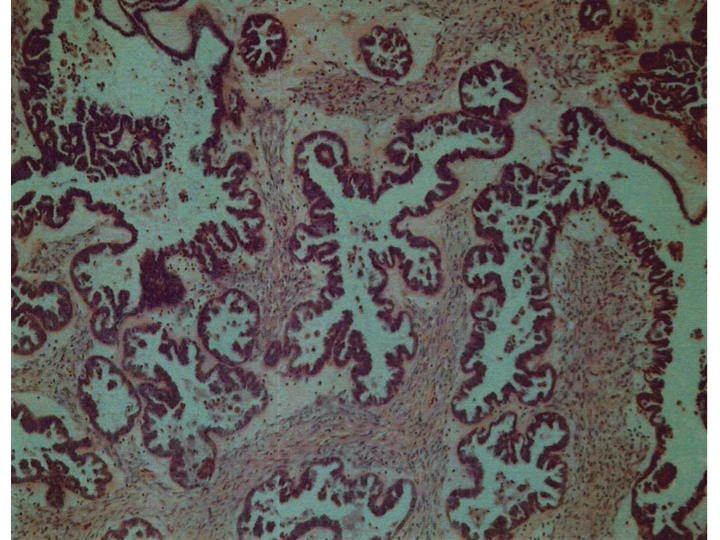

I eventually got a copy of my path report in colour. I didn’t manage to get a photo of my tumour (I asked but some unexpected bleeding during surgery meant the team were otherwise engaged and unable to snap away on their iphones as previously promised…) so this is a good second best. There’s something very cool about being able to “see” this damn BOT.